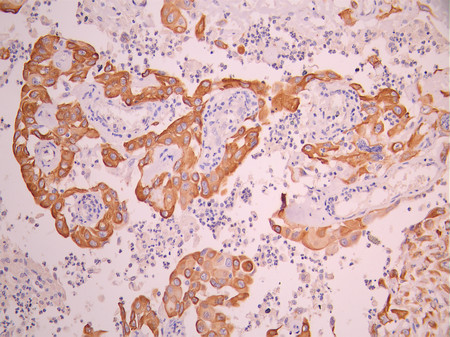

IHC image of CSB-RA957044A0HU diluted at 1:100 and staining in paraffin-embedded human tonsil tissue performed on a Leica BondTM system. After dewaxing and hydration, antigen retrieval was mediated by high pressure in a citrate buffer (pH 6.0). Section was blocked with 10% normal goat serum 30min at RT. Then primary antibody (1% BSA) was incubated at 4°C overnight. The primary is detected by a Goat anti-rabbit polymer IgG labeled by HRP and visualized using 0.05% DAB.